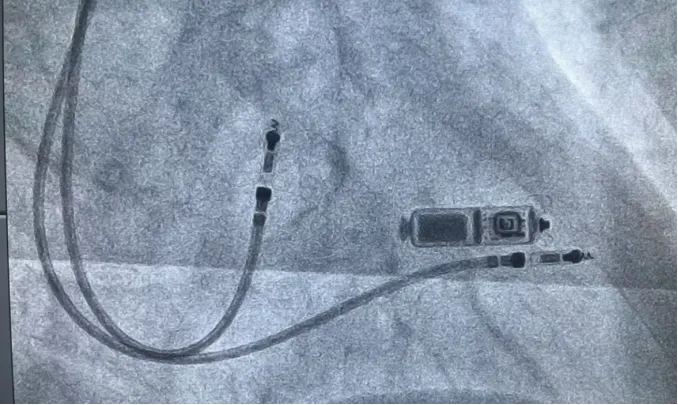

冠心病介入

作为河南省心血管区域医疗中心,除开展常规的冠脉介入治疗,还专注于腔内影像学指导下的复杂冠状动脉介入治疗,不断攻克冠状动脉钙化病变旋磨技术慢性闭塞病变逆向治疗,IABP联合ECMO支持下高危复杂冠脉介入治疗等高难度手术,为区域内的医院提供手术技术援助,多次在全国进行介入手术演示直播,技术水平获得业内高度认可及好评。